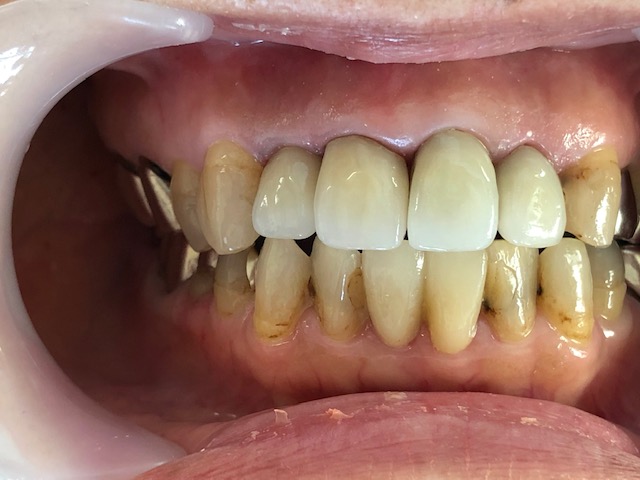

4月のブログの写真を比べれば判ると思いますが、今のところ審美歯科治療を施行した歯は上の前歯4本と下の歯2本です。

今回も、歯周病治療、光殺菌システムペリオウェイブ、審美歯科治療、痛くない治療などを併用した症例でした